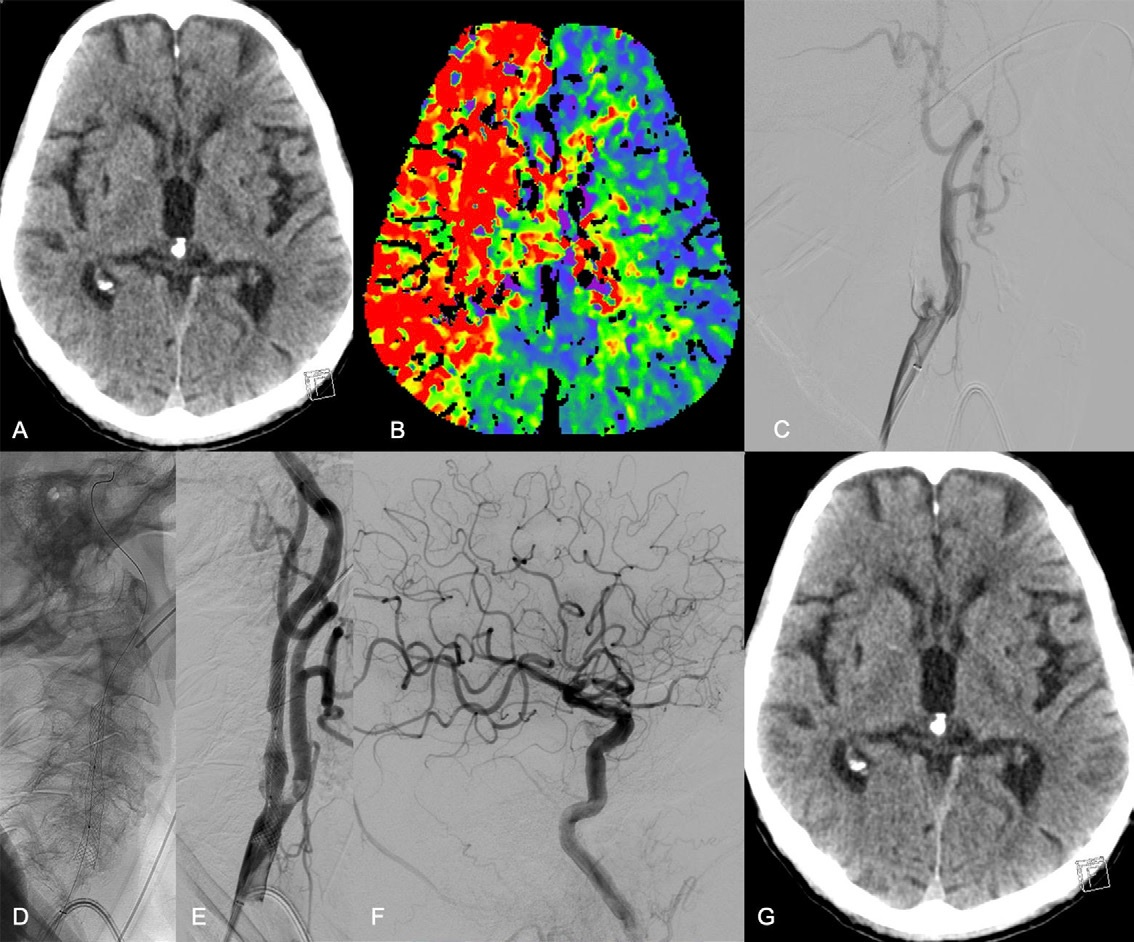

German team supports use of endovascular thrombectomy

Researchers from Hamburg say endovascular thrombectomy is a safe and effective option in cases of acute extracranial internal carotid artery occlusions.